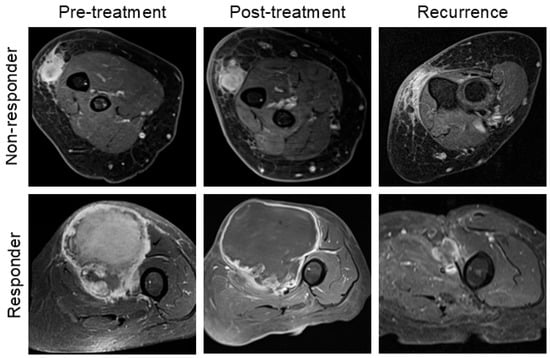

Paradoxical Response to Neoadjuvant Therapy in Undifferentiated Pleomorphic Sarcoma: Increased Tumor Size on MRI Associated with Favorable Pathology

- Valenzuela, R.F.; Amini, B.; Duran-Sierra, E.; Canjirathinkal, M.; Madewell, J.E.; Costelloe, C.M.; Murphy, W.A. Multiparametric MRI for the Assessment of Treatment Effect and Tumor Recurrence in Soft-tissue Sarcoma of the Extremities. J. Radiol. Oncol. 2023, 7, 058–065. [Google Scholar]